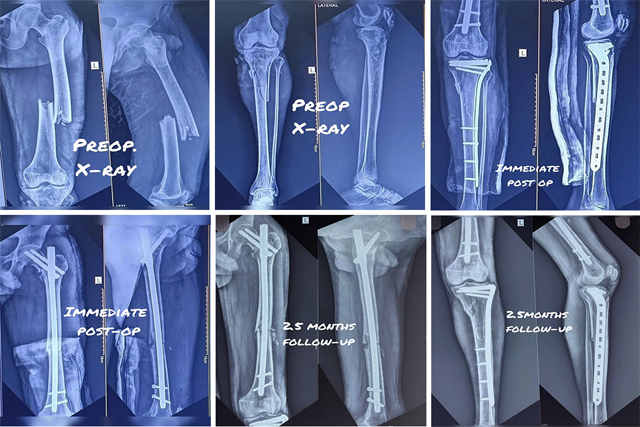

Open reduction and internal fixation (ORIF) for severe proximal tibia fracture

Open reduction and internal fixation (ORIF) for lateral condyle Hoffa's fracture

Open reduction and internal fixation (ORIF) for Polytrauma Fixation